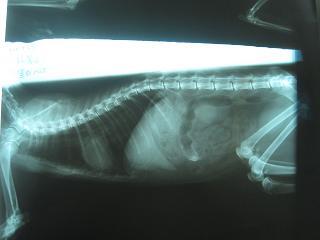

- 編號: 855

主題: 平溪張媽媽的黑白貓(呼吸道感染 拉肚子 黃疸) 治療 申請者姓名: 敏大哥 花色: 申請日期: 2012-08-26 18:56:09 申請者部落格: 申請者臉書網址: 所在縣市/合作醫院: 台北市/詠欣動物醫院 治療費用: 15600元 需求人數: 18人 已結案 (2012-12-08 18:47:42) 報名人員: Cecilia Chang(已付款)、劉蒨(已付款)、劉蒨、Josesol(已付款)、劉蒨、Iris Huang(已付款)、Chang-jie Yang(已付款)、Jimmy(已付款)、Emma Chu、陳倩婷(已付款)、邱小咪(已付款)、OLivia Lee(已付款)、Chiaping Chang(已付款)、Ling(已付款)、juno(已付款)、鍾佳臻(已付款)、鍾佳臻(已付款)、鍾佳臻(已付款)、鍾佳臻(已付款)、鍾佳臻(已付款)、Sky(已付款)、 候補人員: 動物病情說明: 貓咪最近一直食慾不振 蹲坐在角落.送醫治療 先醫治呼吸道 和拉肚子的問題.同時也檢驗傳染病 排除引起食慾不好 發燒 眼睛葡萄膜炎的可能病因.目前強烈懷疑有貓腹膜炎.貓咪仍住院隔離中.先申請一個月的檢查住院費用.